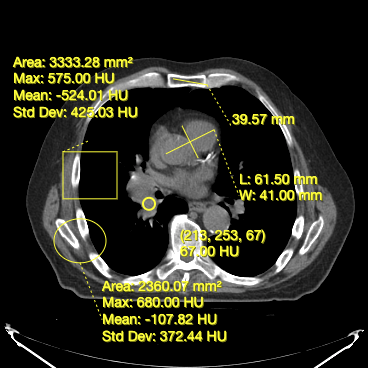

- Measuring width and length for a structure (Bidirectional Tool)

- Measuring area and statistics for a rectangular area (RectangleRoi Tool)

- Measuring volume and statistics for a ellipsoid (EllipseRoi Tool)

- Getting the underlying value for a voxel (Probe Tool)

Below, you can see a screenshot of the annotation tools that are available in Cornerstone3DTools.

Dynamic tool statistics

Cornerstone3DTools is capable of calculating dynamic statistics based on the modality of the volume being rendered. For instance, for CT volumes a ProbeTool will give Hounsfield Units and for PET it will calculate SUV stats.